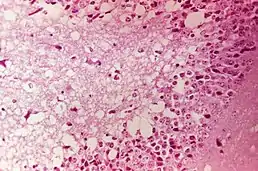

Вірус потрапляє до організму людини внаслідок укусу комара або безпосередньо через слизову оболонку дихальних шляхів. Під час вірусемії, яка триває в середньому 5 днів, досягає нервової системи, спричинює дегенеративні зміни в нервових клітинах головного та спинного мозку. Одночасно уражаються й інші внутрішні органи, зокрема клітини підшлункової залози. Патологоанатомічні зміни властиві енцефаліту та мієліту.